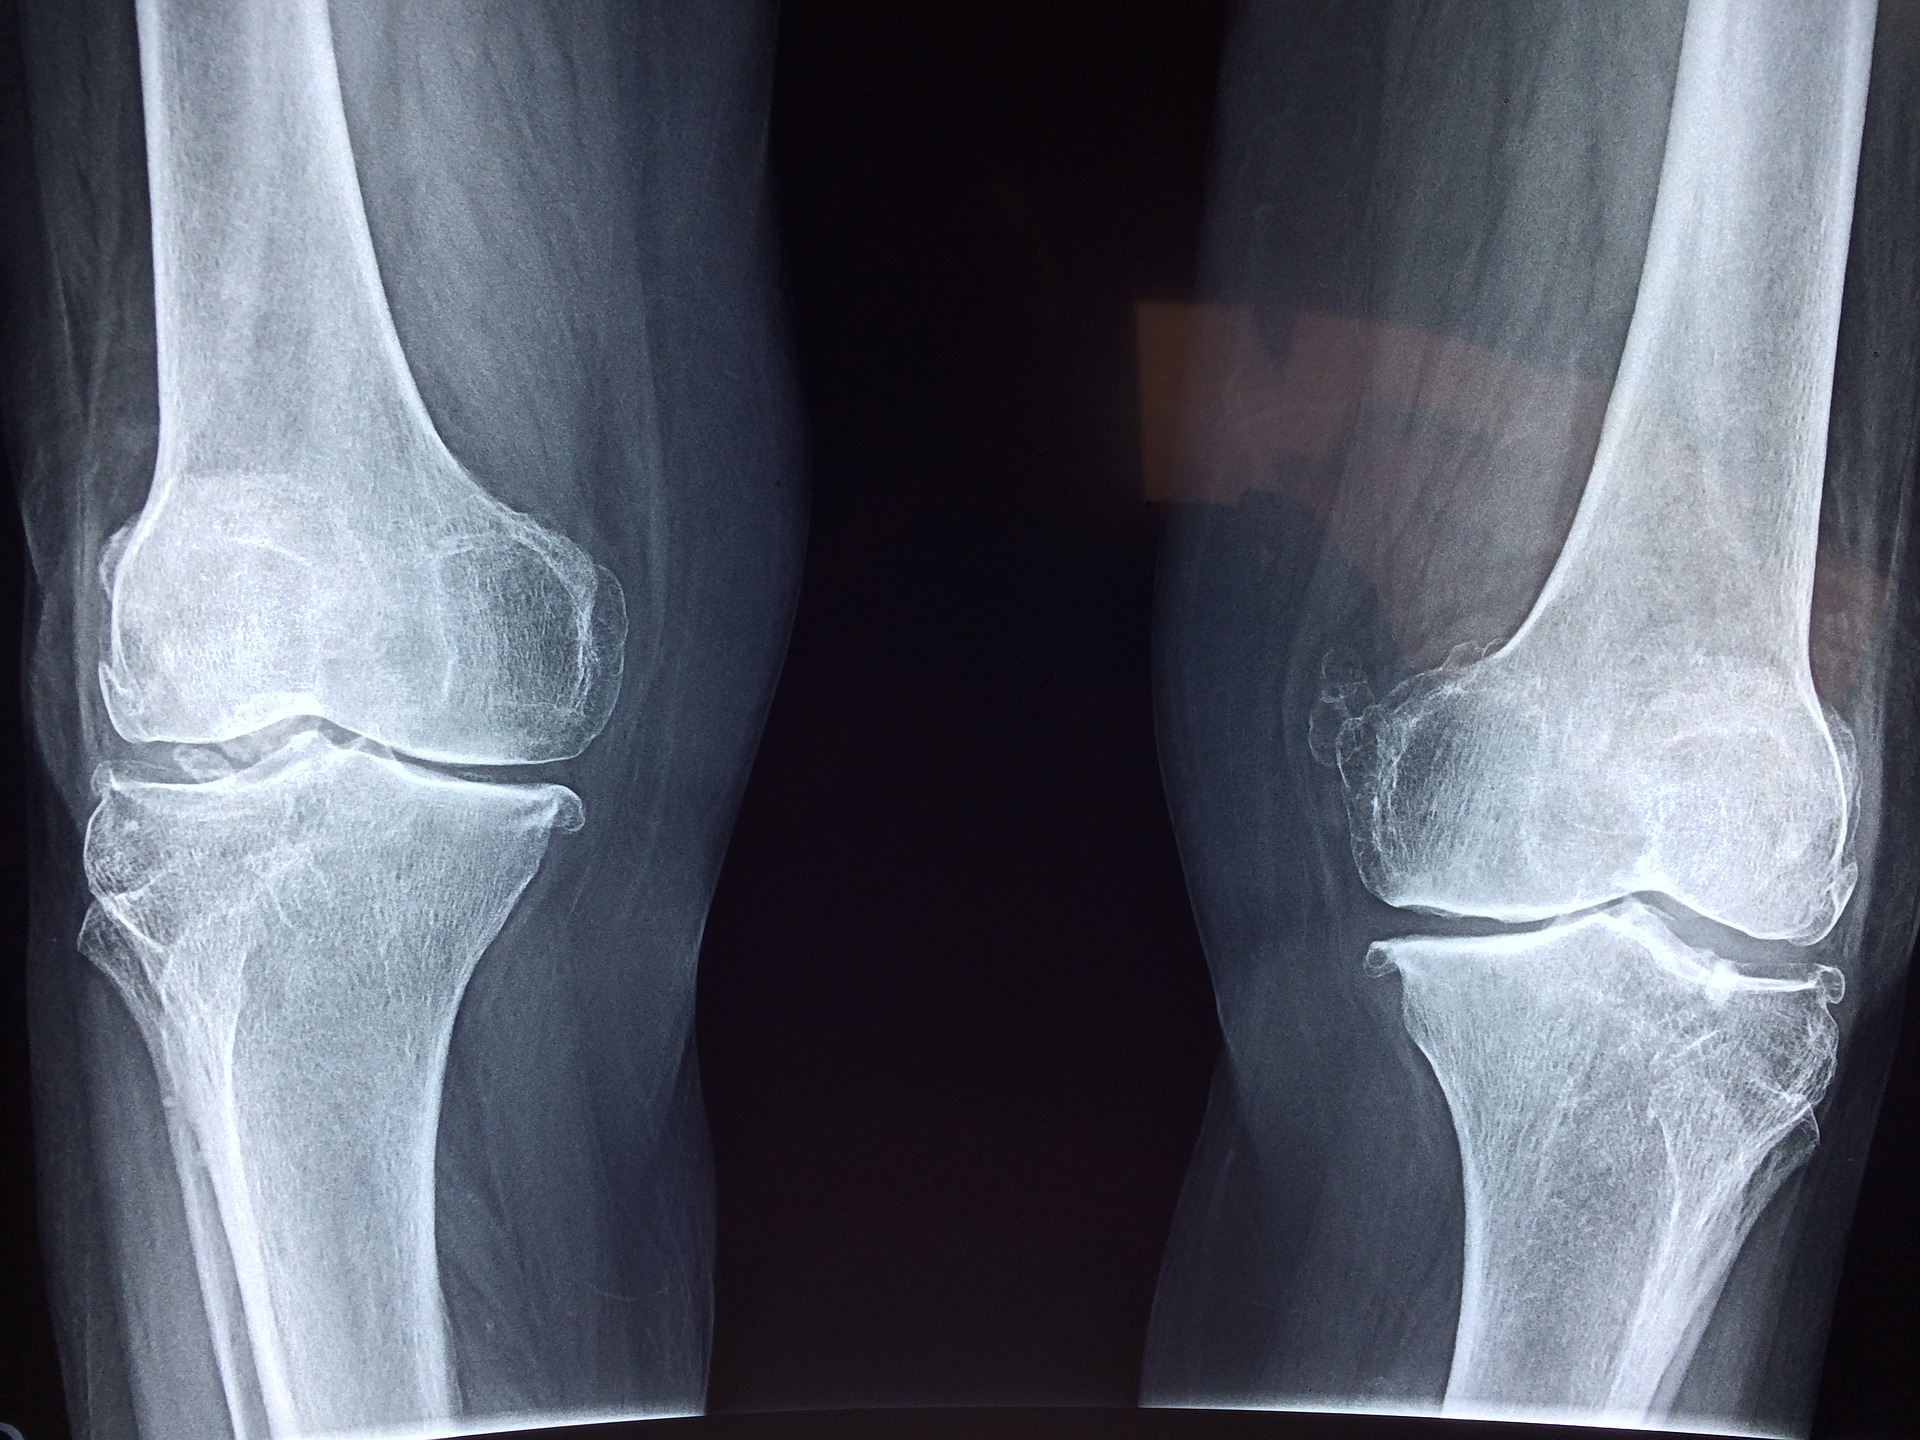

Lékařská poradna: osteoporóza

Trápí vás řídnutí kostí nebo máte obavy z osteoporózy? Jak nemoci předcházet, koho nejvíc ohrožuje a jaké jsou dnešní možnosti léčby?

Na dotazy odpovídá vedoucí lékařka Osteocentra 2. interní kliniky Fakultní nemocnice Plzeň Milena Dolejšová